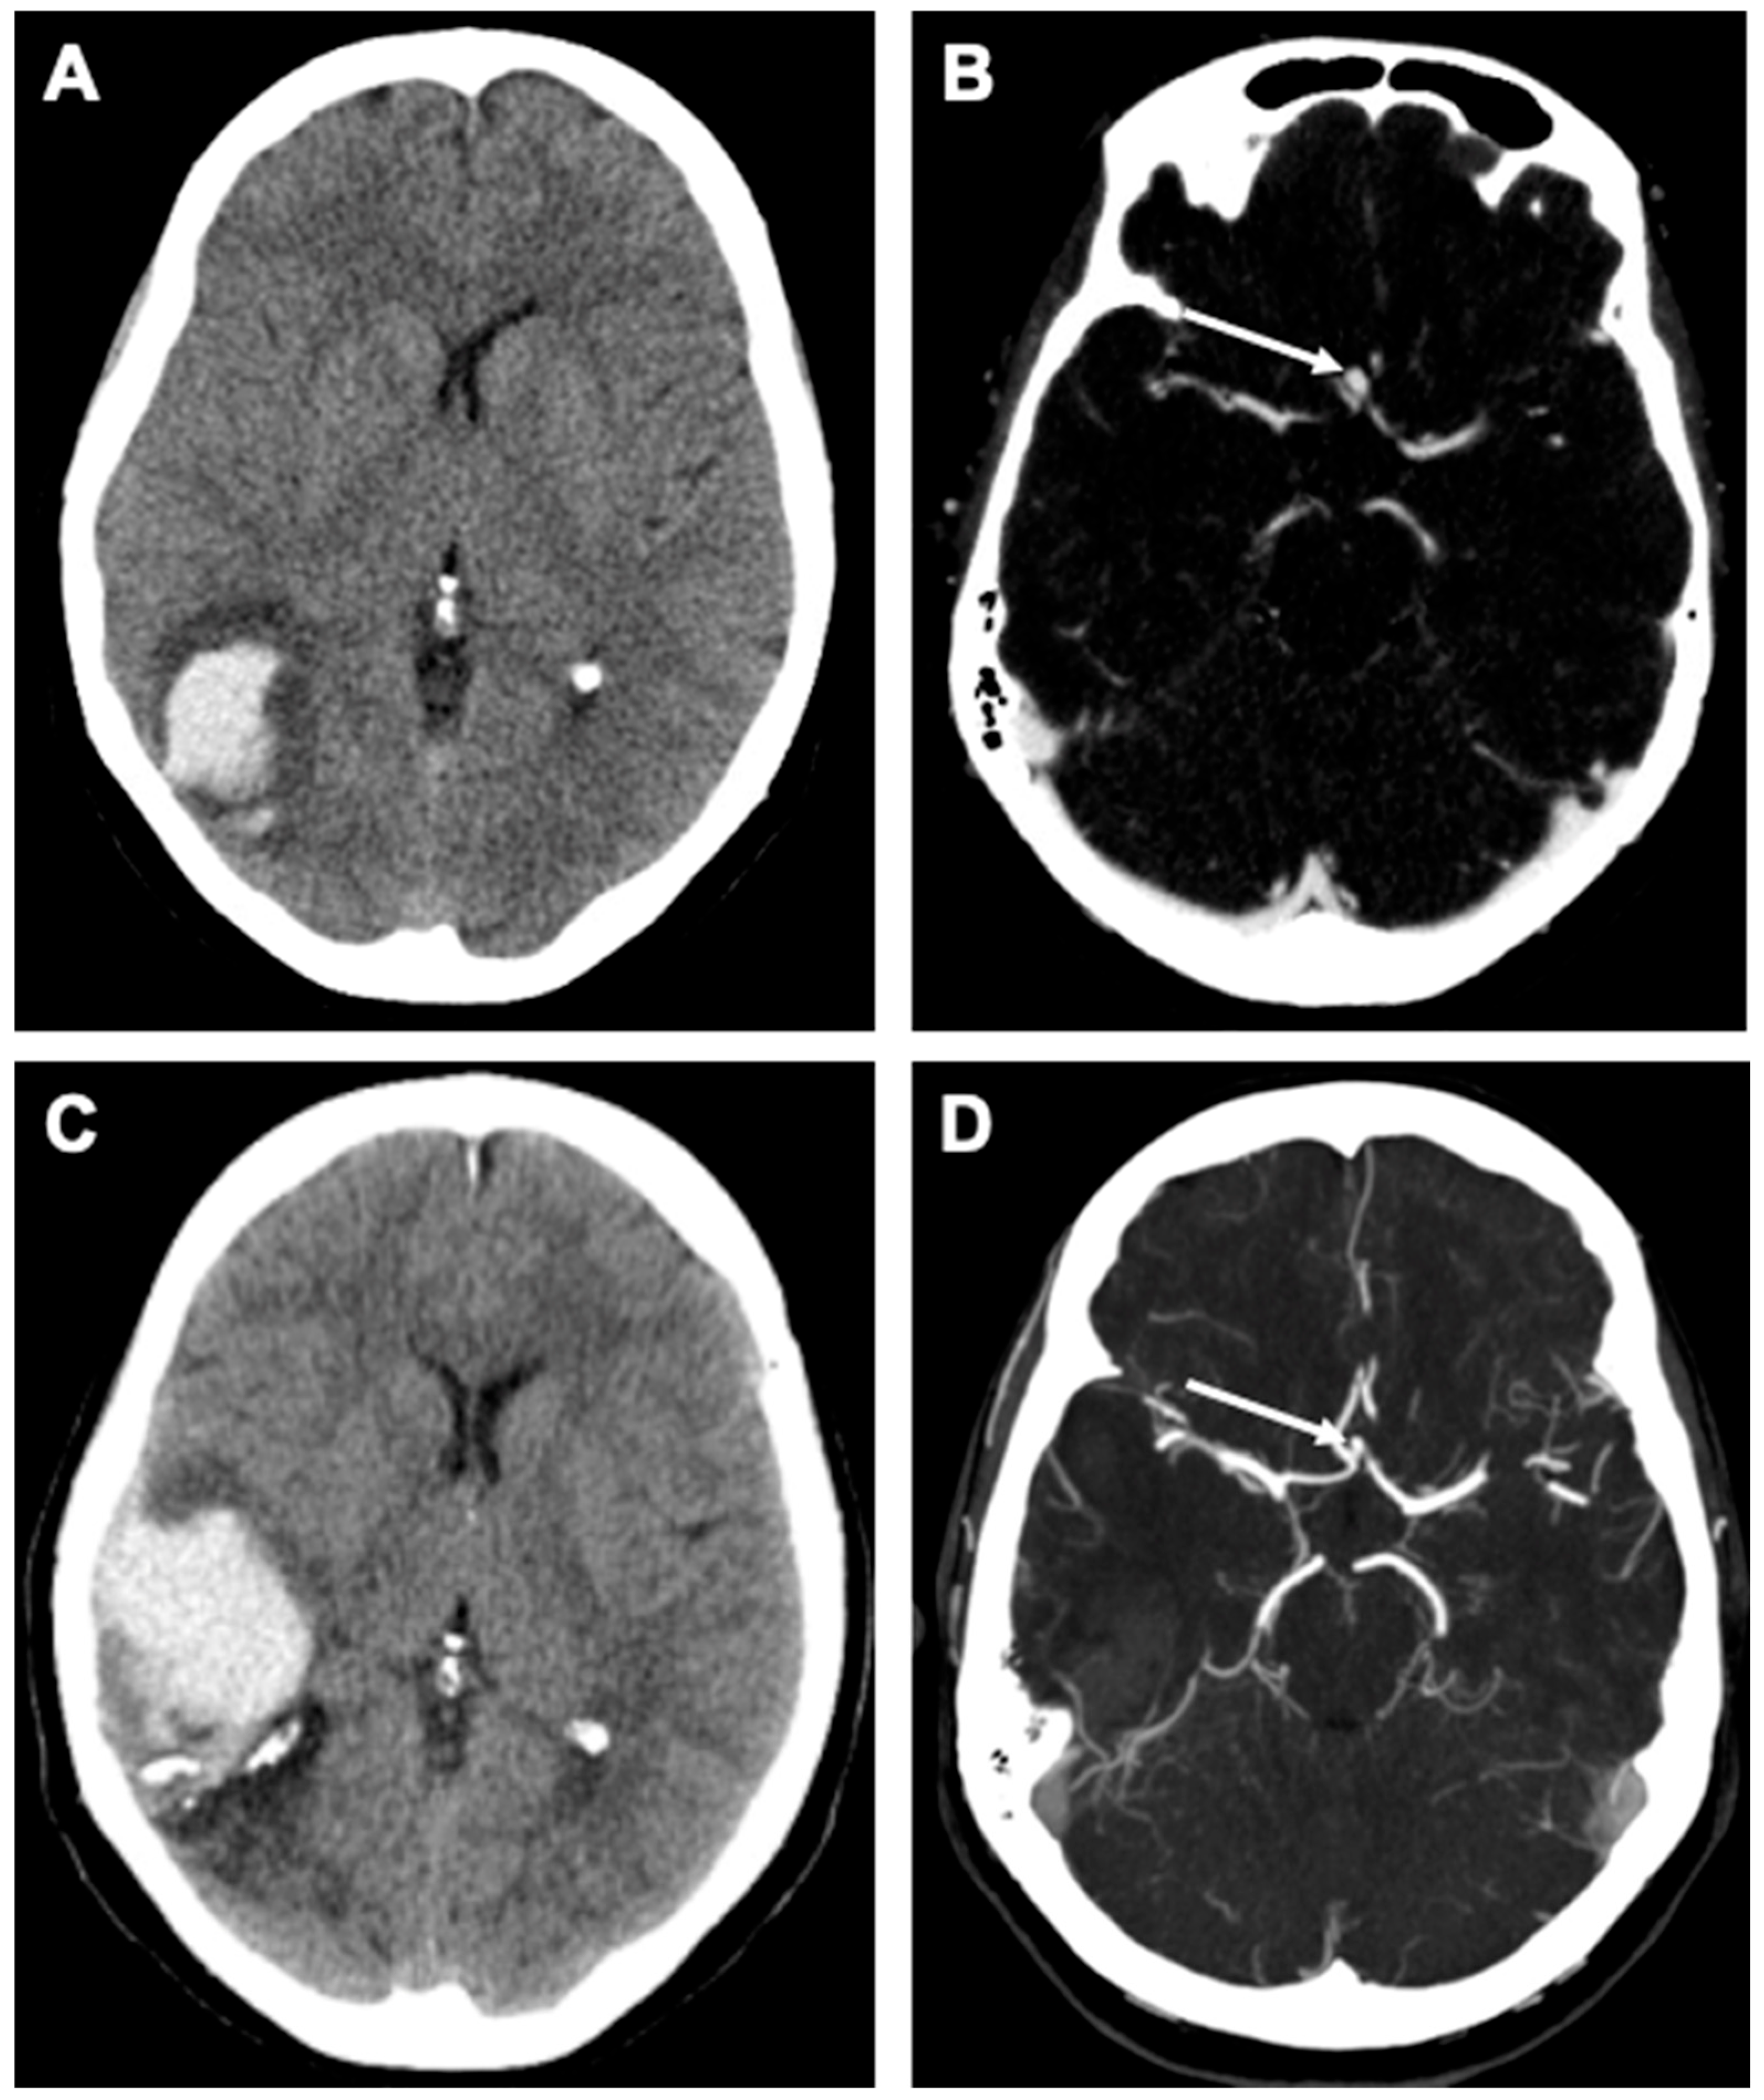

Case Description

2.5. Outcome and Follow-Up